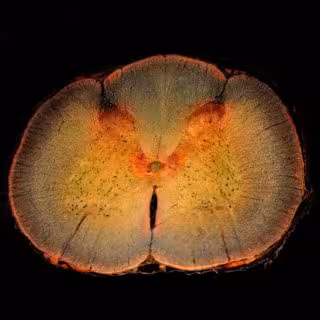

Rediseñan una enzima que podría ayudar a revertir el daño causado por una lesión - DW_ROSS / FLICKR - Archivo

Un equipo de investigadores de la Universidad de Ingeniería de Toronto (Canadá) y la Universidad de Michigan (Estados Unidos) ha rediseñado y mejorado una enzima natural que se muestra prometedora en la promoción de la regeneración del tejido nervioso después de una lesión en la médula espinal.

"Uno de los mayores desafíos para la curación después de este tipo de lesión nerviosa es la formación de una cicatriz glial", detalla la líder del estudio, Molly Shoichet. Una cicatriz glial está formada por células y bioquímicos que se unen fuertemente alrededor del nervio dañado. A corto plazo, este entorno protector protege a las células nerviosas de una lesión mayor, pero a largo plazo puede inhibir la reparación del nervio.

Hace unas dos décadas, los científicos descubrieron que una enzima natural conocida como condroitinasa ABC, producida por una bacteria llamada 'Proteus vulgaris', puede degradar selectivamente algunas de las biomoléculas que componen la cicatriz glial.

Al cambiar el entorno alrededor del nervio dañado, se ha demostrado que la condroitinasa ABC promueve el recrecimiento de las células nerviosas. En modelos animales, puede incluso llevar a recuperar alguna función perdida. Pero el progreso se ha visto limitado por el hecho de que la condroitinasa ABC no es muy estable en los lugares donde los investigadores quieren utilizarla.